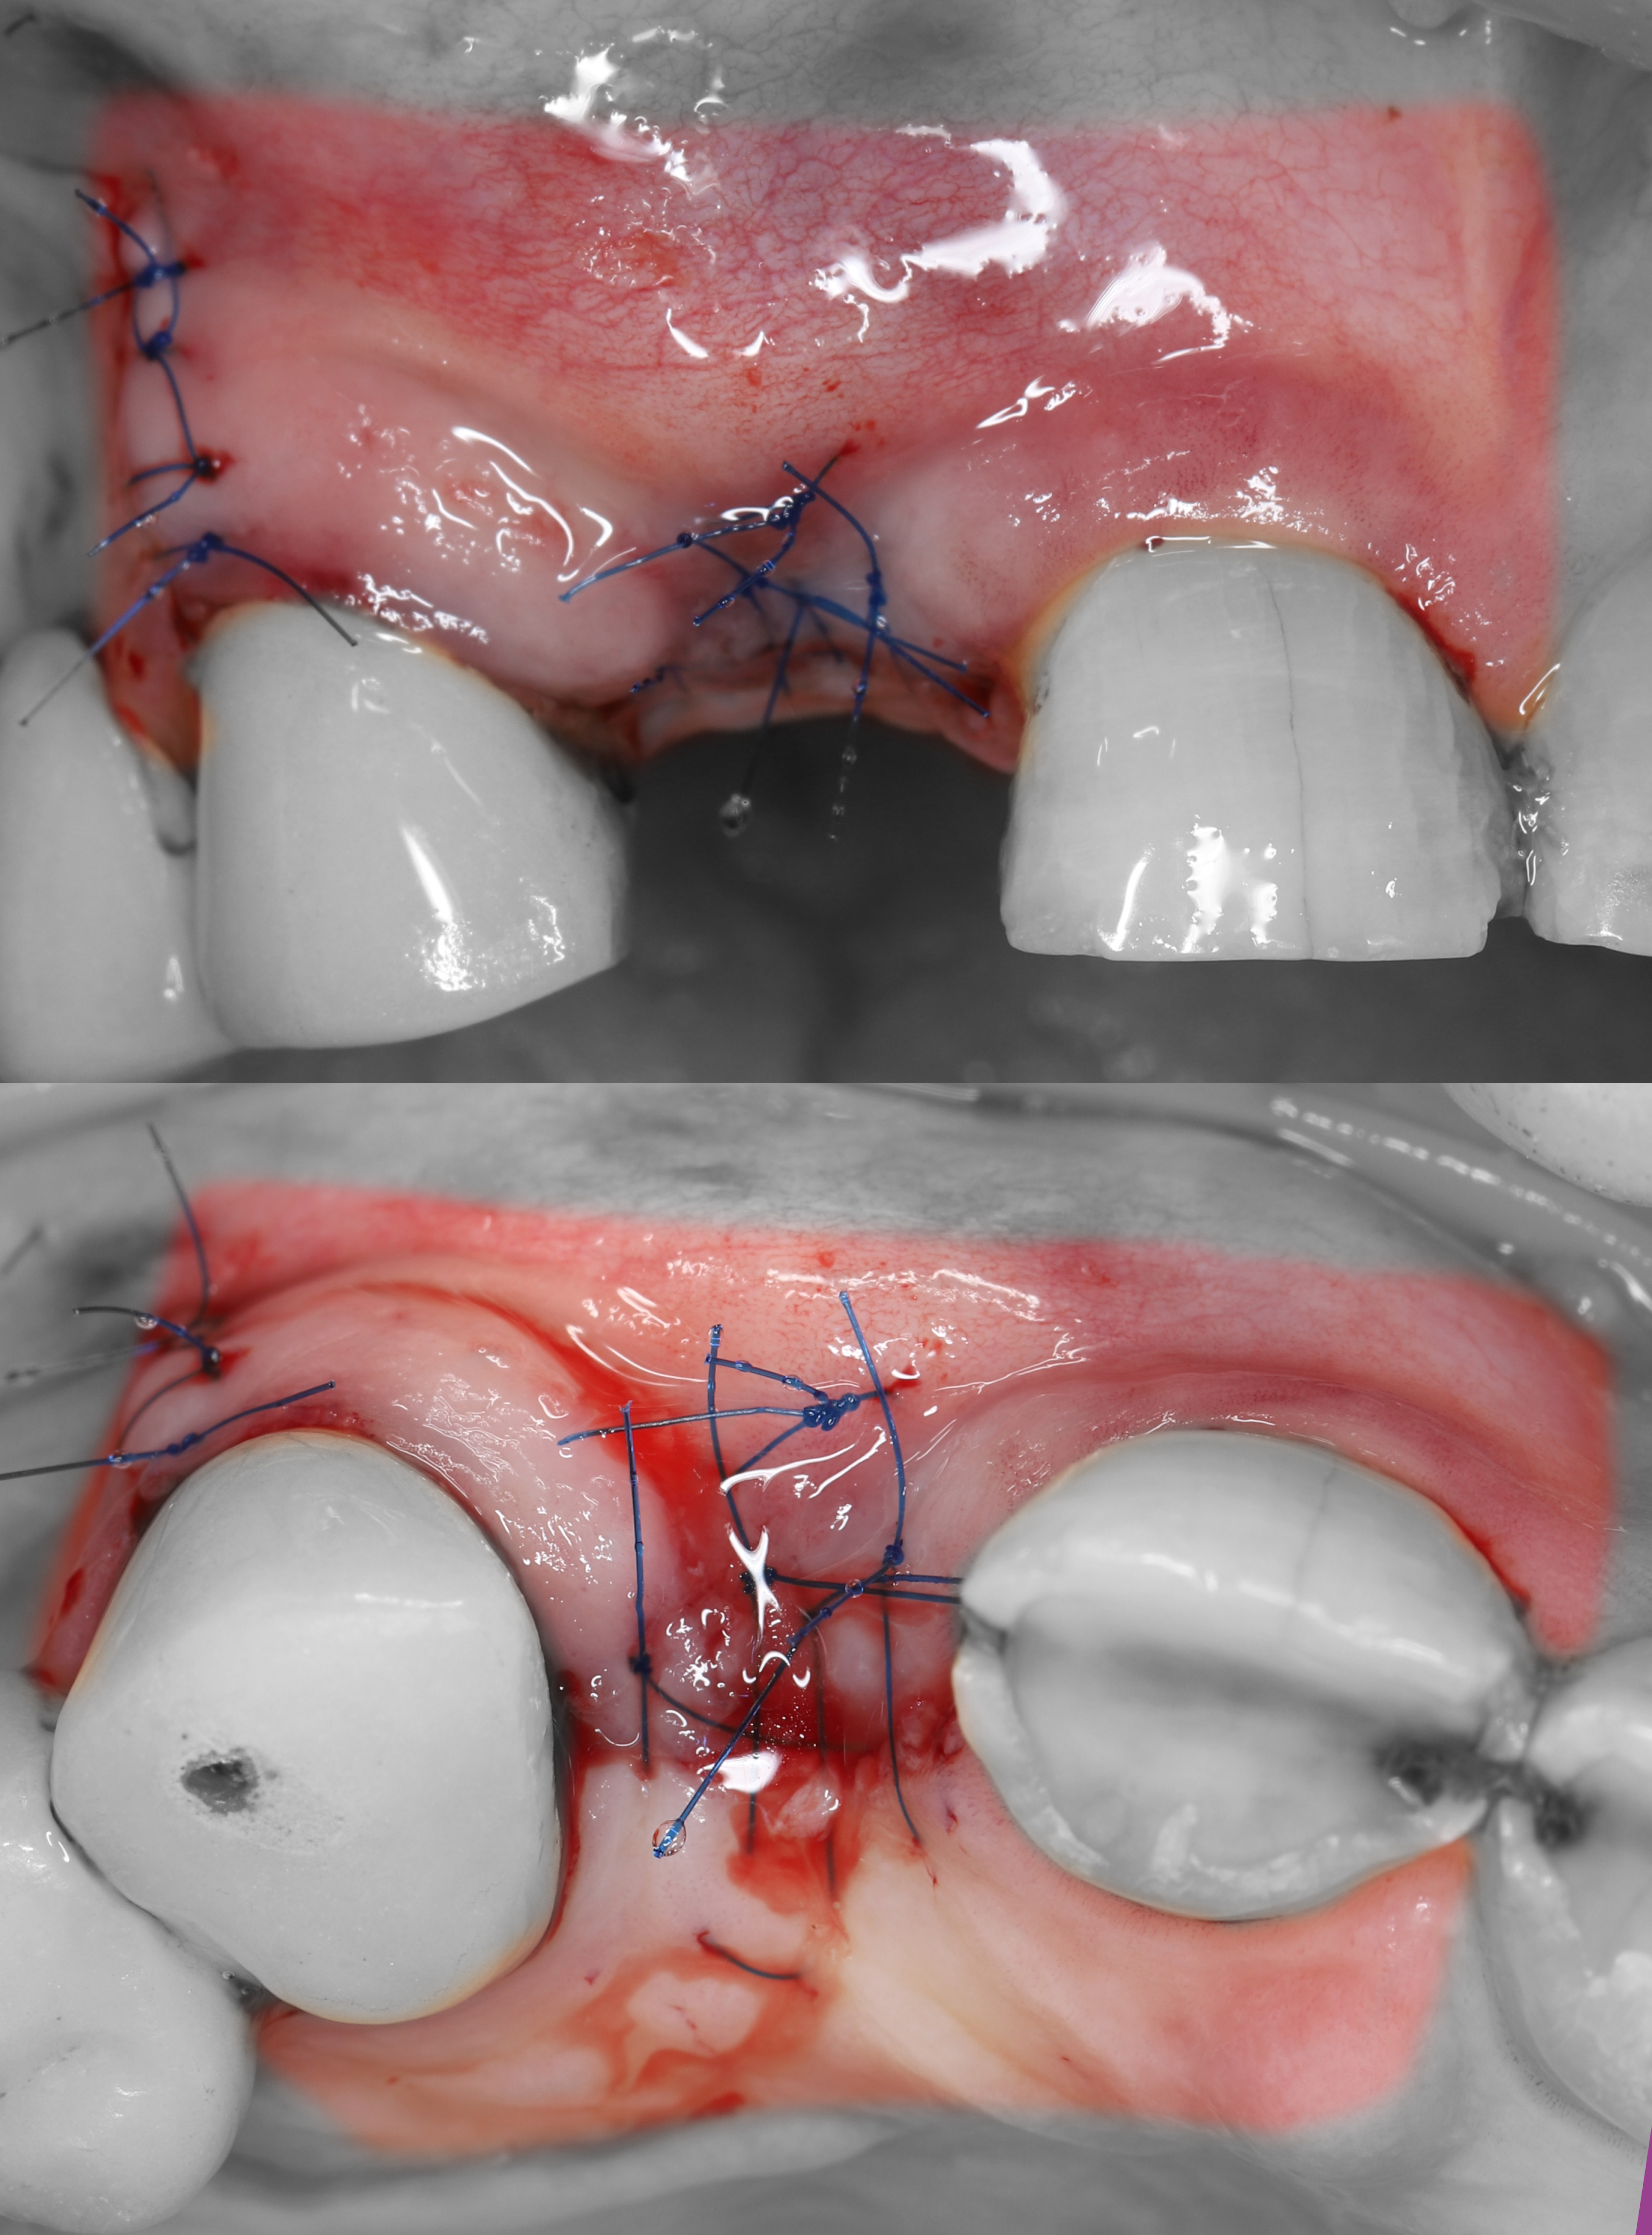

2) Проведены крестальный и вертикальный дистальный разрезы, отслоен СНЛ.

7) Наложены швы Полипропилен 6/0.